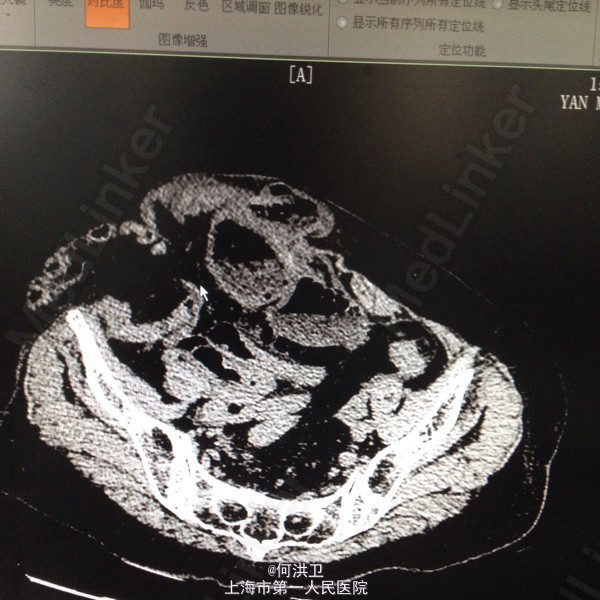

患者86岁女性,因腹痛腹胀半天,停止肛门排气入院,WBC10.85,。四年前有胆结石手术病史,自觉右腹部很软

中上腹压痛,疤痕下方可及8厘米质软包块,活动性差,肠鸣音减弱。CT:腹壁切口疝,内容物为小肠,致机械性肠梗阻

急诊行小肠切除手术加腹壁嵌顿疝回纳修复术。发现:腹腔广泛粘连,腹壁缺损10*13厘米,原切口下方大量肠管网膜从缺口突出,突出肠管见粘连严重并且与腹膜粘连,其中一处小肠对系膜侧坏死穿孔,直径3厘米,腹腔大量肠内容物和腹水